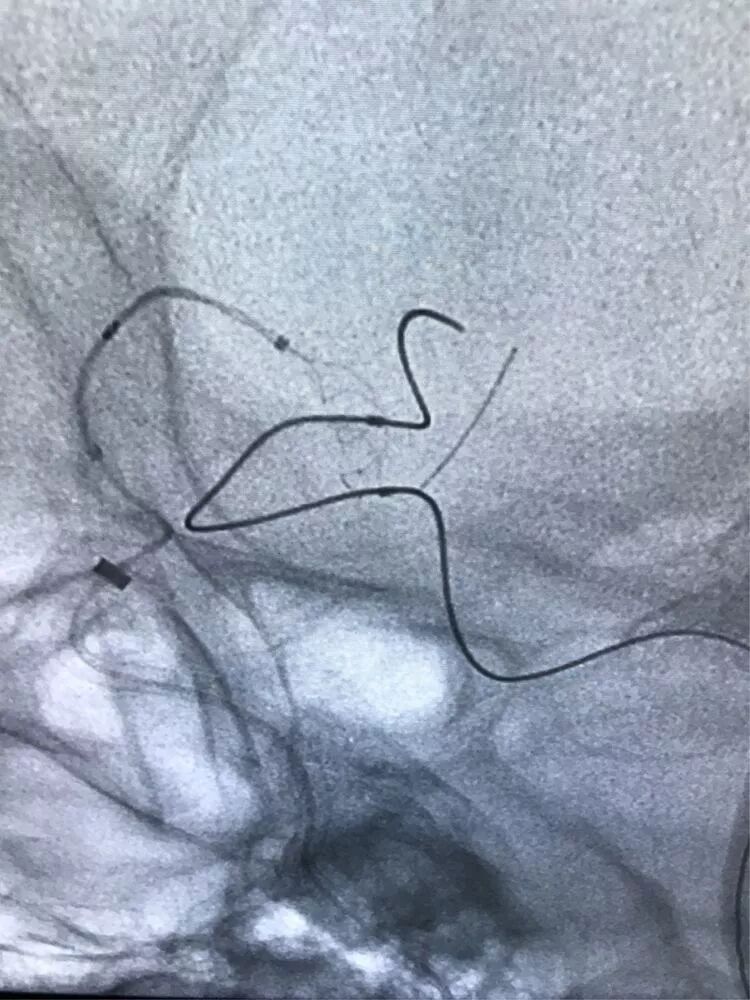

双侧穿刺置鞘,对侧90cmCOOK长鞘+115cmNavien导引导管 ,导引导管头端尽量走得远一些

输送支架的微导管从右侧通过前交通动脉进入左侧

大脑前动脉与颈内动脉之间的夹角太小,导致微导管从大脑前动脉进入颈内动脉遭遇了一些困难

终于将导丝送入了后交通动脉以远

输送支架的微导管终于到位了,输送弹簧圈的微导管到位比较容易

释放支架